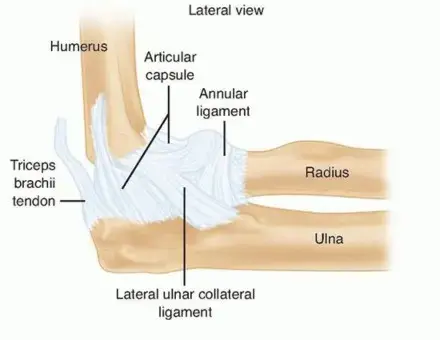

لفهم طبيعة الإصابات التي قد تصيب المرفق ومفصل الترقوة الأخرمي، من الضروري الإلمام بالتشريح الأساسي لهذين المفصلين الحيويين.

تشريح مفصل المرفق

مفصل المرفق هو مفصل زلالي معقد يتكون من ثلاثة عظام رئيسية:

عظم العضد (Humerus):

العظم الطويل في الذراع العلوي.

عظم الزند (Ulna):

أحد عظمي الساعد، ويشكل الجزء الأكبر من مفصل المرفق، خاصةً من خلال الناتئ المرفقي (Olecranon) والناتئ الإكليلي (Coronoid Process).

عظم الكعبرة (Radius):

العظم الآخر في الساعد، والذي يتصل بالعاتق في مفصل المرفق من خلال الرأس الكعبري (Radial Head).

تُحاط هذه العظام بمحفظة مفصلية قوية وتدعمها شبكة من الأربطة التي تمنحها الثبات وتحد من حركتها في اتجاهات غير مرغوبة:

الرباط الجانبي الزندي الوحشي (Lateral Ulnar Collateral Ligament - LUCL):

يُعد هذا الرباط حاسماً في استقرار المرفق، ويمنع خلع المرفق الخلفي الوحشي. غالباً ما يتضرر في إصابات ثلاثي الرعب.

الرباط الجانبي الزندي الإنسي (Medial Ulnar Collateral Ligament - MUCL أو MCL):

يوفر ثباتاً ضد قوى الإجهاد الأروح (Valgus Stress).

الناتئ الإكليلي (Coronoid Process):

بروز عظمي على عظم الزند، يعمل كحاجز أمامي يمنع خلع المرفق للخلف. كسره يساهم بشكل كبير في عدم استقرار المرفق.

الرأس الكعبري (Radial Head):

بالإضافة إلى دوره في حركة الدوران، يعمل كـ "مثبت ثانوي" ضد قوى الإجهاد الأروح ويساهم في الاستقرار الدوراني للمرفق.